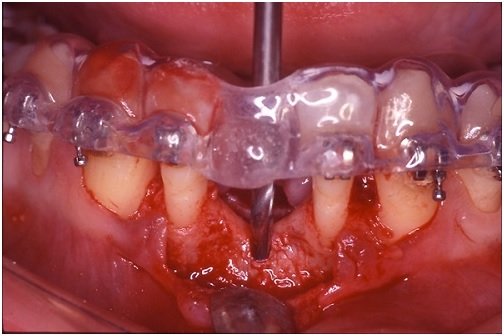

Para que um guia realize adequadamente as suas funções, ele precisa estar adaptado à região cirúrgica, sem atrapalhar a visualização e o acesso do cirurgião (Figura 1). Essas são condições bastante difíceis de serem garantidas, uma vez que um aparelho acrílico volumoso e intimamente relacionado com a área cirúrgica quase sempre dificulta o acesso e a visualização dos tecidos que irão receber o implante. Assim, falando francamente, a maioria dos cirurgiões não gosta de usar o guia. Eu não gosto nem um pouco. Nós acabamos usando outras referências, como os dentes adjacentes e antagonistas, para posicionar o implante corretamente. Isto é um erro (que eu cometo frequentemente) que pode custar caro na hora da confecção da prótese.

Figura 1 – Guia cirúrgico em posição e perfuração com broca de 2mm sendo executada. Observar a boa visualização do campo operatório com facilidade de acesso.